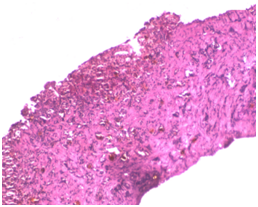

Liver biopsy (LB)

Percutaneous LB in early infancy under local anesthesia and sedation is a safe procedure, if performed by competent physicians.4,33 LB is the single most definitive investigation in the evaluation of NC. In several single center studies, a diagnosis of BA was correctly suggested by LB histological findings in 90 to 95% of cases and avoid unnecessary surgery in patients with intrahepatic disease (Figure 19).1,10,34 Rastogi et al. also reported that sensitivity, specificity and accuracy of liver biopsy in the diagnosis of BA are 89-99%, 82-98% and 60-95%, respectively.4,35 The diagnostic histologic appearances of BA include bile duct proliferation, bile plugs in the portal tract bile duct, portal tract edema and fibrosis (Figure 20). Liver histology also useful for the diagnosis of other specific conditions, such as A1AT deficiency, some metabolic liver diseases, Alagille syndrome, neonatal sclerosing cholangitis, and viral infection (CMV or herpes simplex).10 Presence of steatosis indicates metabolic liver diseases. Rarely LB may yield pathognomic findings of storage disorders.

Figure 18: Liver biopsy in a case of BA (Picture was taken with permission).

Figure 19: Biliary atresia. Significant ductular proliferation, cholestasis and portal fibrosis (H&E x 100).

Figure 20: Intrahepatic cholestasis with inflammed cell infiltration (left) and hepatocute degeneration (right).